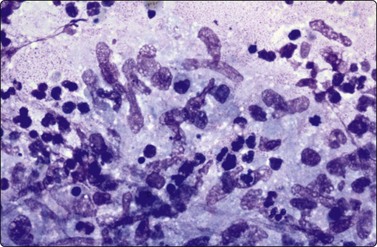

Sarcoidosis has distinctive rounded epithelioid granulomas infiltrated by lymphocytes without necrosis, but its diagnosis requires negative AFB stains, mycobacterial cultures and PCR with the correct clinical presentation and serology (Fig. 18.7).42

image image

Fig. 18.7 (A) Cohesive rounded sarcoid granuloma with occasional lymphocytes (Giemsa,

×400); (B) Rounded sarcoid granuloma (Pap, ×400).